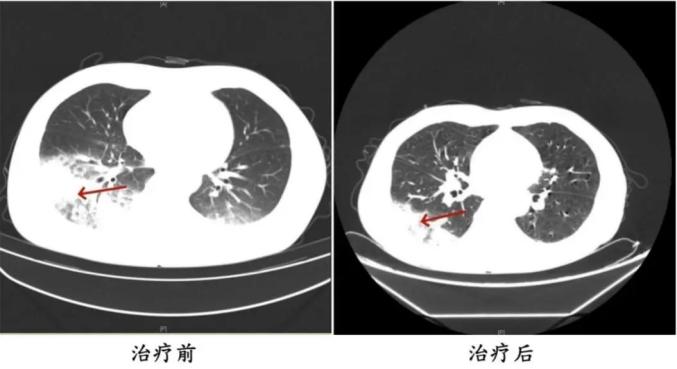

2024年,55岁的湖南长沙市民陈先生(化姓)有许多过去的历史,如2型糖尿病、2型糖尿病性肾病、慢性肾功能不全等。他去医院看病,因为他继续发烧、发抖、干咳。检查发现肺部感染严重。抗生素抗感染治疗后效果不佳,患者持续发烧,出现异常表现。医生询问后发现,陈先生之前开车出差。因为天气热,他开了一台很久没清洗的汽车空调。他每天在车里呆十几个小时,回来后就出现了上述症状。经检查,最终确诊为军团菌肺炎。

治疗前后陈先生肺部CT影像